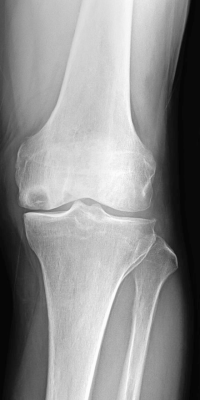

人工膝単顆置換術術前

当科で行っている主な手術は、骨折全般、変形性膝関節症に対する人工膝関節置換術(全置換、単顆置換)や高位脛骨骨切り術、膝半月板損傷に対する関節鏡手術、変形性股関節症に対する人工股関節置換術、神経・腱・血管に対する微小外科を含む手外科手術、肩腱板断裂に対する修復術、変形性肩関節症に対するリバース型人工肩関節置換術などです。

なお、人工膝関節置換術においては、症例に応じてナビゲーションの使用やオーダーメイド人工膝関節(PSI=Patient Specific Instrument)を用いた手術を行っております。また、人工股関節置換術においては、筋肉や腱の損傷を最小限にする低侵襲アプローチによる手術を行っております。